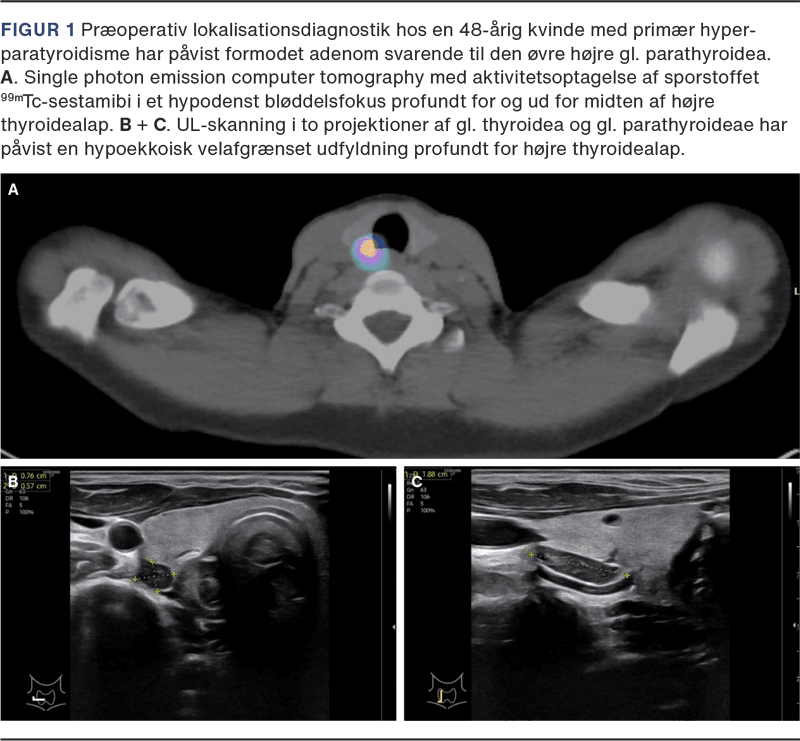

Operation for PTHP tilstræbes udført ved fokuseret PTX (se nedenfor), idet 90% kun har én hyperproducerende kirtel [12, 13]. Et fokuseret og derfor mindre indgreb forudsætter præoperativ lokalisation af patologisk parathyroideavæv (Figur 1), som oftest er i relation til gl. thyroidea men kan ligge i området fra basis cranii og ned til mediastinum (ektopisk placering).

CT med kontraststof og sestamibiskintigrafi er begge meget benyttede. Et dansk studie har sammenlignet metoderne og fandt subtraktionsteknikken overlegen [12]. Cholin-PET/CT, som udføres hurtigere og med mindre stråledosis, har vist sig at give tilsvarende gode resultater [13]. UL-skanning af gl. parathyroideae benyttes i stigende grad [14] og er i enkelte afdelinger for nylig indført som den primære billeddiagnostiske modalitet. UL kræver særlig erfaring og er svær at foretage hos patienter med multinodøs struma, højt BMI samt ved dybe eller ektopiske parathyroideadenomer. Samtidig har den teknologiske udvikling af UL-skannere gjort det muligt at lokalisere mindre adenomer.